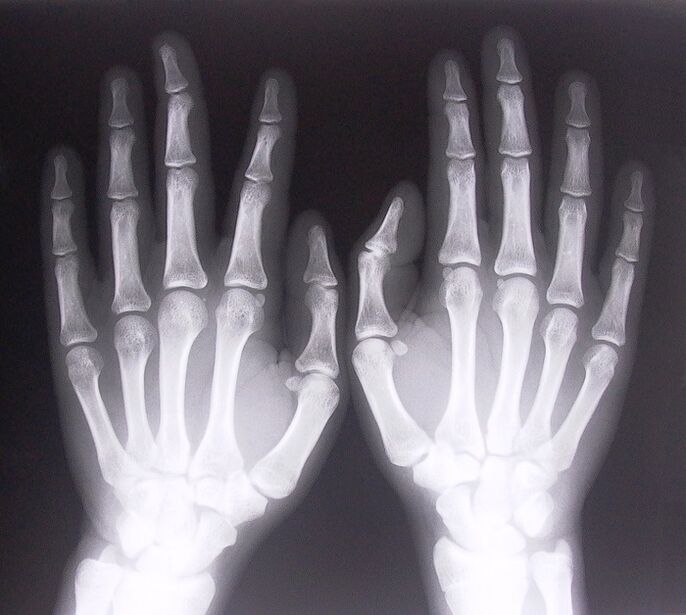

1. Faceți radiografii.

Raze X ca modalitate de a diagnostica durerea în articulațiile degetelor